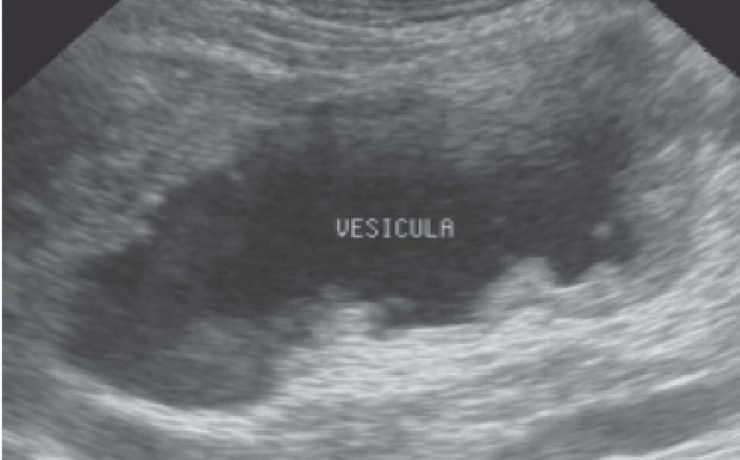

Hiperplasia prostática benigna y la utilidad del ultrasonido para su diagnóstico

La próstata es una glándula localizada en la cavidad pélvica del hombre, detrás del pubis, delante del recto y debajo de la vejiga. Envuelve y rodea el primer segmento de la uretra justo por debajo del cuello vesical. Es un órgano de naturaleza fibromuscular y glandular. Tiene forma de pirámide